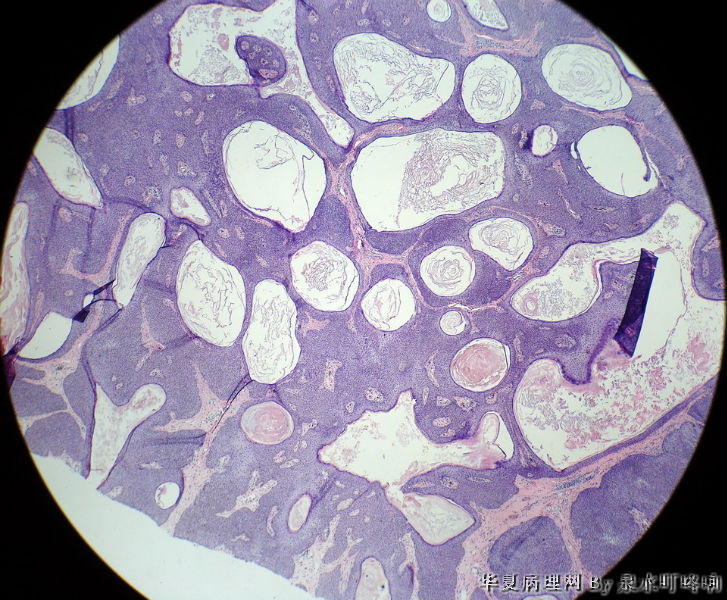

男,80岁,左耳后肿物十余年。

参考诊断

棘层肥厚型脂溢性角化症